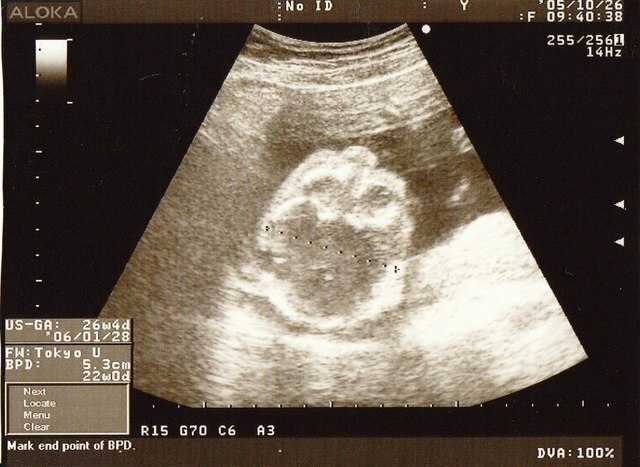

妊娠7ヶ月(24週~27週)の妊婦さんの状態

赤ちゃんの動きが活発なのでいろいろなポーズが見られる時期でもあります。そのため多くの赤ちゃんの性別が判明している頃です。ただしこれは個人差が大きいです。

妊娠7ヶ月は胎動が最も盛んになってきます。赤ちゃんの脳が発達するので、自分で体を動かすことが活発になります。加えて、子宮も大きくなり羊水も増加する頃です。

胎動がよく分からない場合は、健診時にお医者さんと一緒に確認すると良いでしょう。エコーで見ると回転したりキックしていたり、あくびをしていたりします。

妊娠7ヶ月の胎児の大きさ、状態